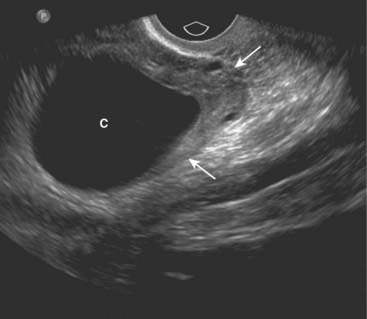

image If a gestational sac (the earliest sonographic finding in pregnancy, appearing at about 4-5 weeks gestational age), yolk sac (first structure to be seen normally in gestational sac), or viable fetus is identified in the uterine cavity, an ectopic pregnancy is effectively excluded. Endovaginal examinations are usually performed to find the gestational sac (Fig. 19-26).

image

Figure 19-26 Early intrauterine pregnancy.

There is a single live intrauterine pregnancy (solid white arrows) contained within the gestational sac (solid black arrow) inside the uterus (U). Using a measurement called the crown-rump length, (between the white arrows) the embryo (E) was estimated at 9 weeks of age. Sonographic gestational age begins on the first day of the last normal menstrual cycle because, for most individuals, that is a more certain date than the actual date of ovulation.

image Conversely, the demonstration of a live embryo outside of the uterus is diagnostic of an ectopic pregnancy. This is not a common occurrence with most ectopic pregnancies (Fig. 19-27).

Figure 19-27 Ectopic pregnancy.

A, A normal endometrial stripe (solid black arrow) is present with no evidence of a pregnancy in the uterus (U). B, There is an adnexal mass (solid white arrow) containing an embryo (E). There is fluid in the cul-de-sac (C). The demonstration of an embryo outside of the uterus is diagnostic of an ectopic pregnancy.